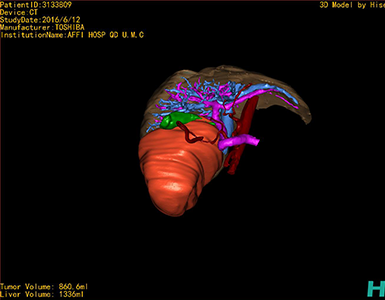

通过调节窗宽窗位调整CT序号,对肿瘤,肝实质,胆囊,下腔静脉,肿瘤,肝动脉、门静脉及肝静脉等进行三维重建;系统自动计算肿瘤体积和肝脏体积。

模拟手术操作,自动计算切除肿瘤体积。肝脏体积为1336ml,肿瘤体积为860.6ml,肿瘤体积为肝脏体积的64.4%,通过比对30-40岁正常肝脏体积为1323.35±298.47 ml,通过术前模拟手术,精准判断切除后剩余肝脏体积能耐受,避免肝衰竭发生。

术前手术方案的规划。

术前三维重建:重建图片